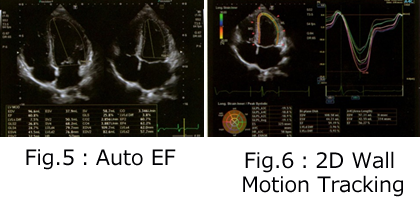

放射線部門が担当するのは、①X線撮影(レントゲン)・X線透視 ②CT撮影 ③超音波検査です。